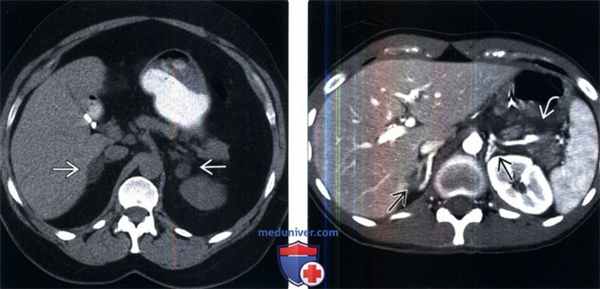

(Слева) У пожилой женщины с синдромом Кушинга, низким уровнем АКТГ и аномально низким уровнем дексаметазона на бесконтрастной КТ выявлены увеличенные узловатые надпочечники Лапароскопическая адреналэктомия подтвердила диагноз АКТГ -независимой макронодулярной гиперплазии.

(Справа) У молодого мужчины в состоянии шока после тупой травмы на контрастной КТ визуализированы «выступающие» гиперконтрастированные надпочечники и перипанкреатический отекй. Гиперденсность надпочечников признак гипоперфузионного комплекса. Умеренное увеличение надпочечников также можно рассматривать как системную стрессовую реакцию.